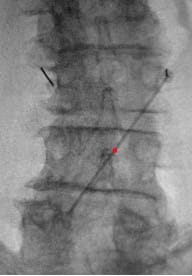

- In PA view, introduce guide needle just off midline from the superior L4 SP border towards the ipsilateral L3 TP–SAP junction marker; in lateral view, advance anteriorly to TP to traverse L2–L3 intertransversarii (~45°).

- In the lateral view, advance the guidewire towards the inferior dorsal L2 body; adjust depth if resistance is encountered. Prior to removing the guide needle and exchanging for the introducer sheath/dilator, use a #11 scalpel to make a stab incision along the guide needle trajectory adjacent to the L4 SP to create room for the introducer sheath/dilator.

- Advance introducer sheath/dilator over guidewire past TP; remove guidewire/dilator.

- Insert lead anterior to TP; retract introducer sheath to deploy lead and confirm tine engagement around intertransversarii via push–pull test under low-dose live fluoroscopy in lateral and AP view.

- Repeat on the contralateral side.